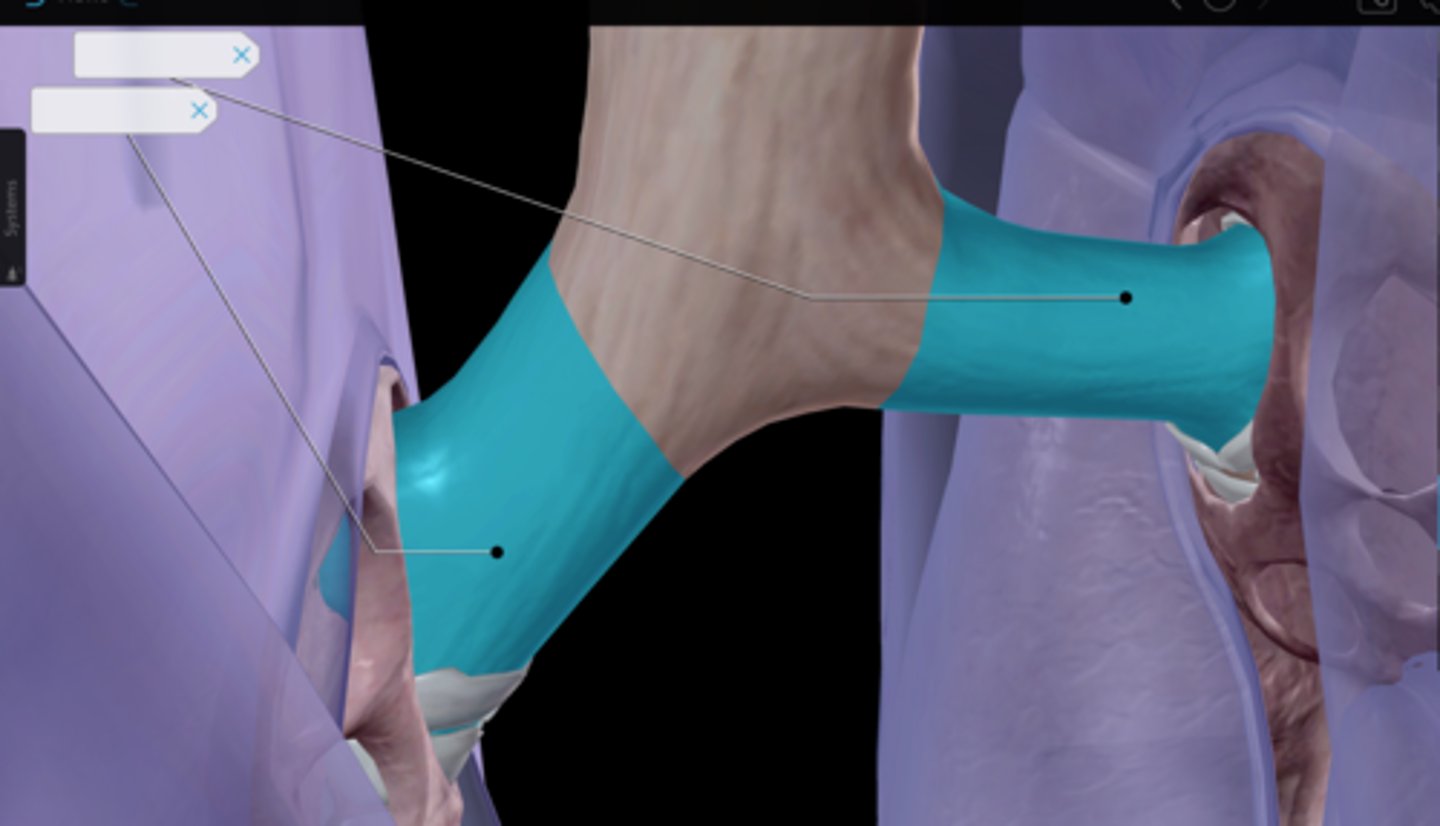

Trachea

Tracheal cartilaginous rings